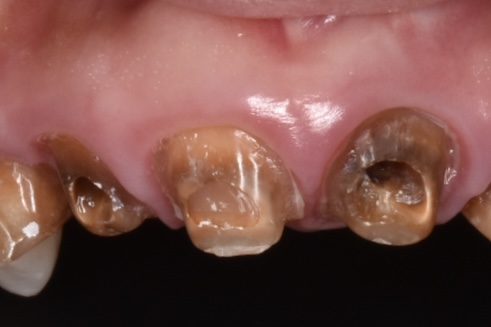

穴だけ開いた歯の状態

神経処置が未処置のまま放置?の歯です。実は下のCTの写真でわかる様に歯の変形があります。ご本人様にお伺いしたところ昔前歯を強打した経験があるとの事でしたが、当時は受診せず経過を診ていたそうです。セラミック治療した歯科ではこの変形した歯について何も伝えられなかったと。。。